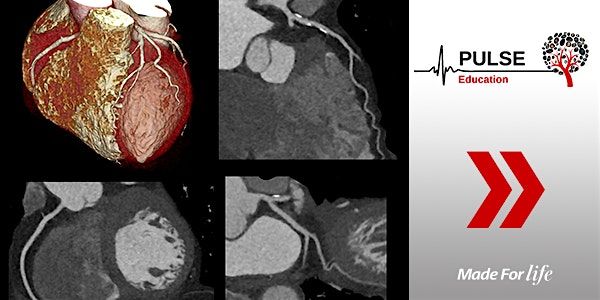

Day 1 will include information on patient preparation, ECG concepts, anatomy, scan techniques and troubleshooting.

Day 2 will consist of a practical session that covers cardiac CT post-processing using the Vitrea advanced visualisation software for Calcium Scoring and CT Coronary Angiography for routine and bypass graft cases. Each participant will have their own workstation.